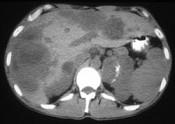

问题 男,37岁,阵发性高血压1月余,请结合所提供图像,选择最佳答案()

选项 A.左侧肾上腺癌 B.左侧恶性嗜铬细胞瘤 C.左侧肾上腺转移瘤 D.肝转移瘤 E.原发性肝癌

答案 BD